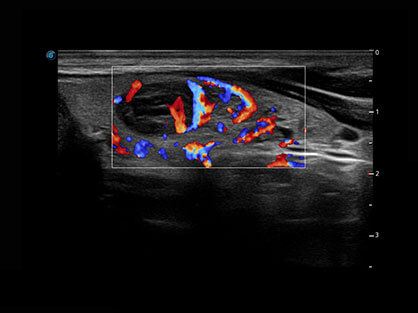

• Wi-Flow

通过对组织运动信息、血流信号及背景噪声进行准确智能的阈值判定,高效提取出微弱血流信号,获得高灵敏度和空间分辨率的血流图像,为临床提供更加真实和丰富的诊断信息。

临床图